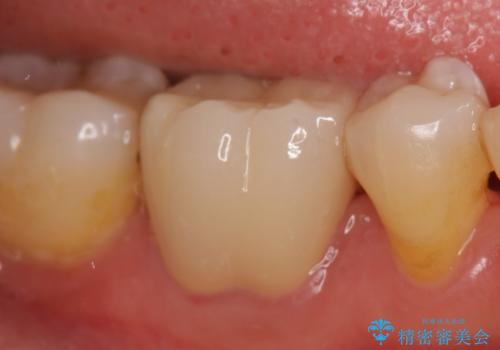

- 右下6番目の銀歯が気になるのでセラミックにしたいといらっしゃった方の症例です。

銀歯及び虫歯を除去後、オールセラミッククラウンによる補綴を行いました。

今回用いたオールセラミッククラウンはジルコニアフレームという白い素材の上にセラミックを盛っているため、審美性が非常に高いのが特徴です。

また、ジルコニアは人工ダイヤモンドの材料にも使われているほど高い強度を持っており、そのためオールセラミッククラウンは審美性だけでなく、奥歯やブリッジの補綴も可能とするクラウンです。